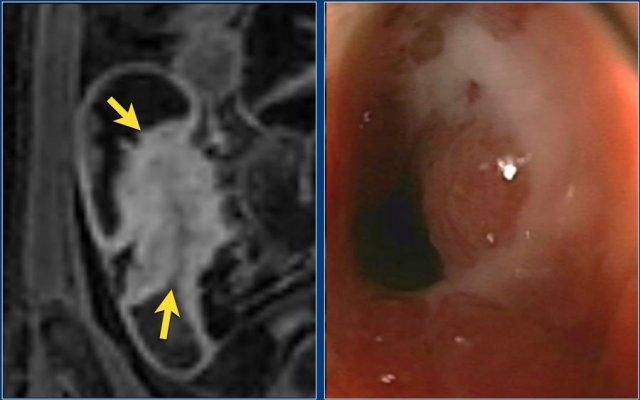

Hình ảnh T1 coronal sau tiêm thuốc tương phản từ và T2 có fat-sat cho thấy nhiều ổ loét nhỏ tại hồi tràng cuối.

Loét

Loét vừa đến sâu có thể thấy trên hình ảnh T1W và T2W, nhưng các ổ loét nhỏ có thể khó phân biệt với các nếp niêm mạc tùy thuộc vào mức độ căng giãn lòng ruột.

Các ổ loét là điểm viêm đang hoạt động và thường có ngấm thuốc tăng trên hình ảnh T1W sau tiêm thuốc tương phản từ.